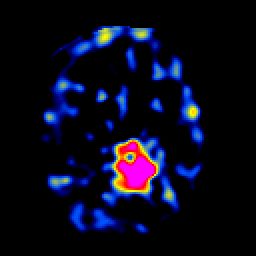

SPECT TL Study #5 -- Slice #34

[Home][Help][Clinical][Tour 1][Tour 2][Tour 3] Slice 34